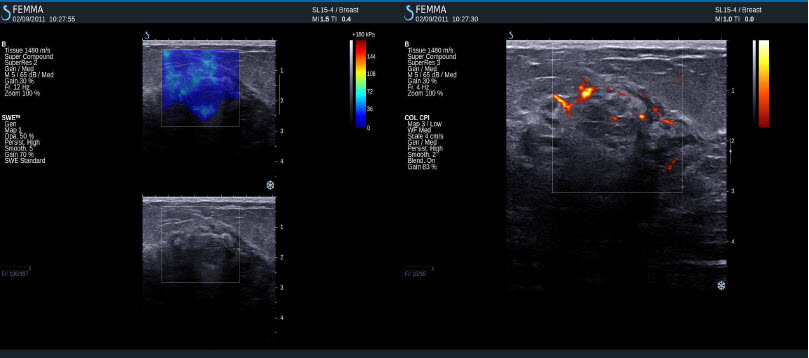

Maligní tumor (IDC)

Invazivní duktální adenokarcinom